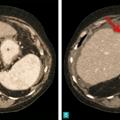

Carcinome hépatocellulaire

TUMEURS DU FOIE

CARCINOME HEPATOCELLULAIRE

Image typique de CHC